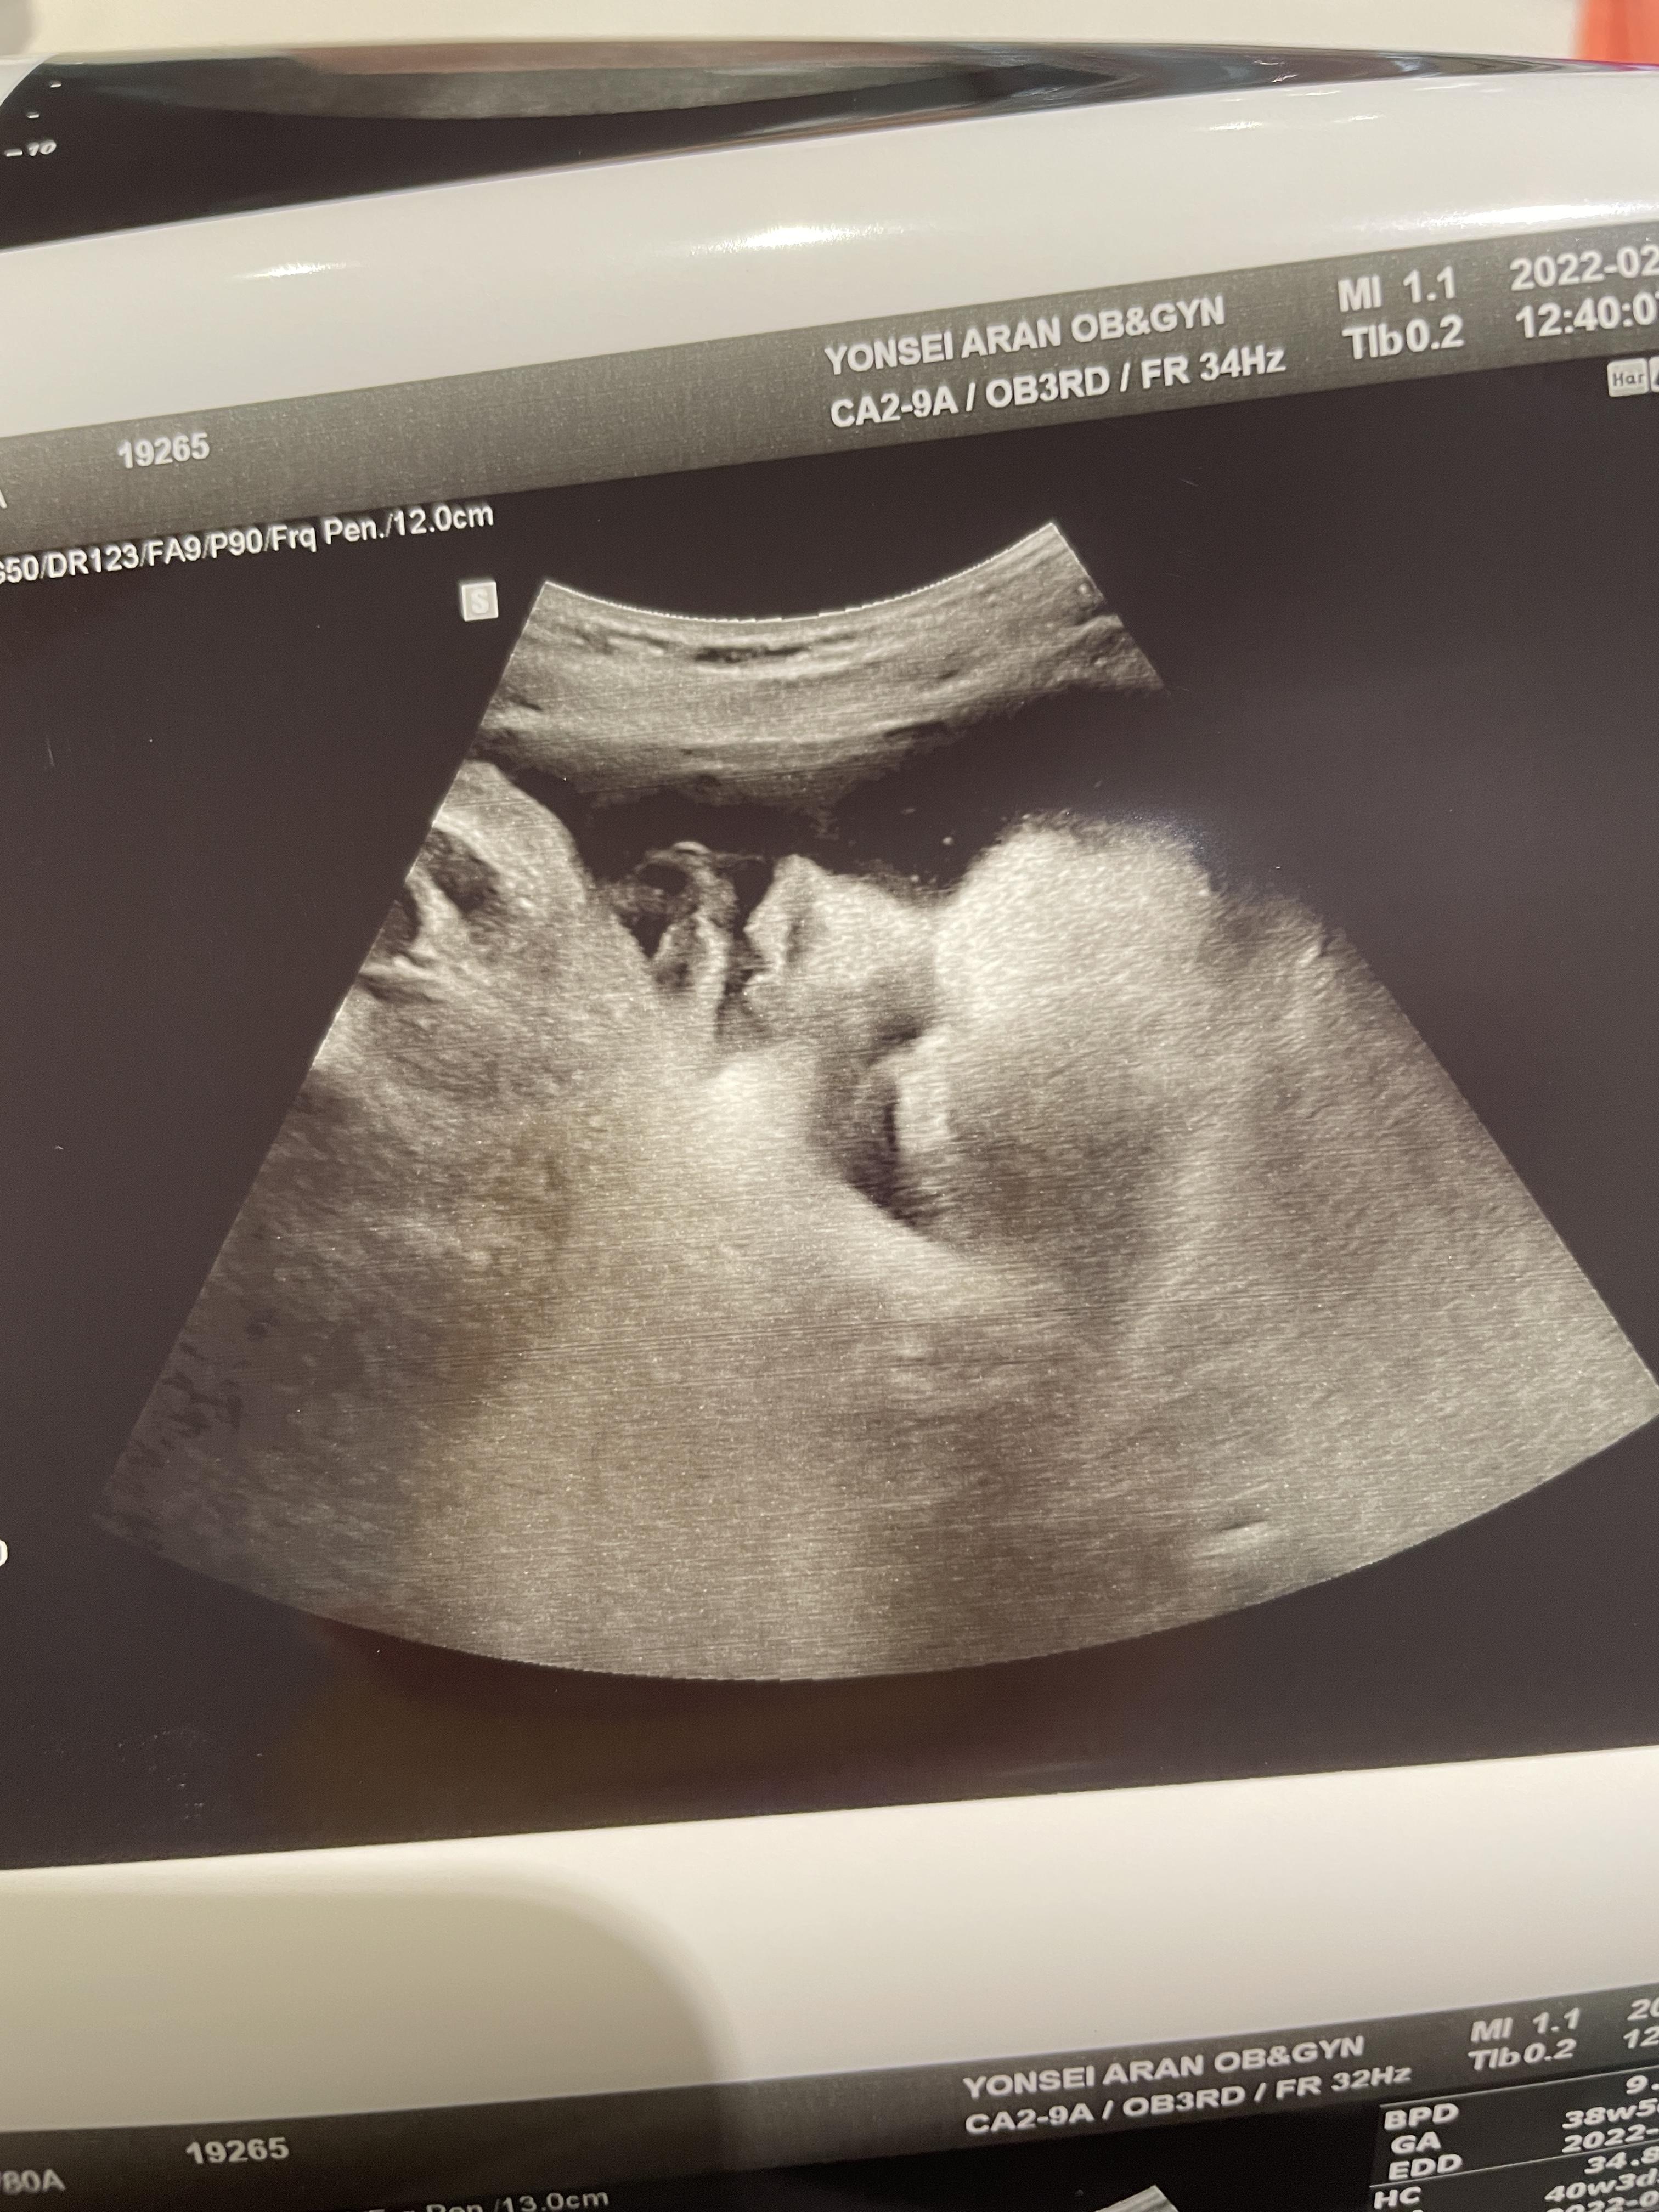

애기가 얼굴이 너무 잘보인다며 웃으셨다.

하나도 안내려왔다고...ㅠ

그와중에 머리는 역시 커졌고,